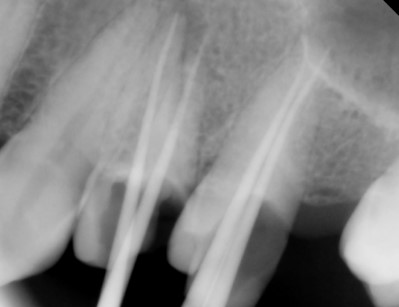

- Unhealthy pulp is removed. The length of the root canal is determined with the help of Electronic Apex locators as well as radiographs. The canals are then cleaned, enlarged and shaped with special caliberated instruments and disinfecting solutions.

- Periodic Radiographs (X rays) using digital RVG are taken during the treatment.

- Once the tooth is free of infection, the tooth is filled with a special root canal filling material like gutta percha and the access previously opened is sealed permanently with a Core filling.